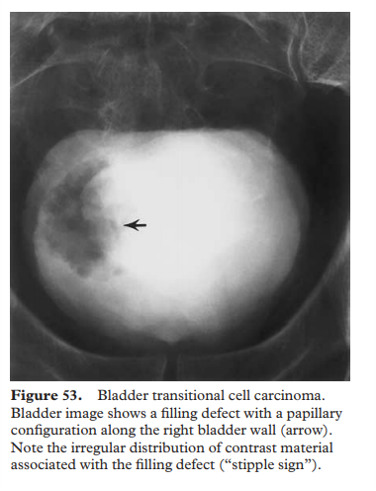

multifocal TCC